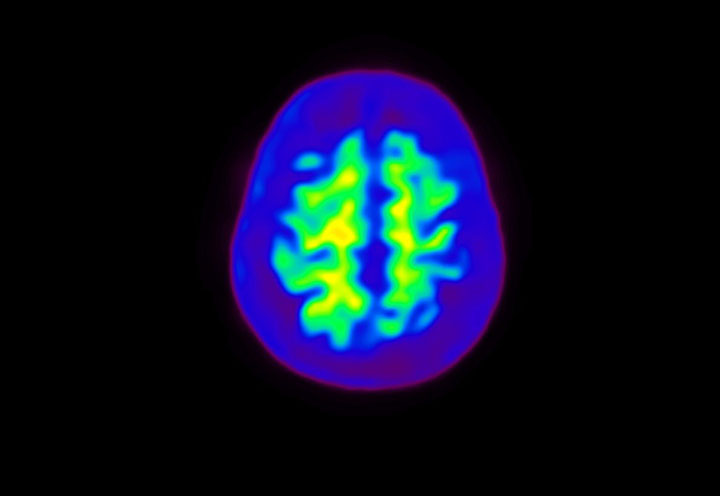

Head / Case4 : Amyloid

Courtesy : Kindai University Hospital

- Injected dose: 3.21 MBq/kg, 18F-Flutemetamol

- Uptake time: 100 minutes

- Scan time: 20 minutes